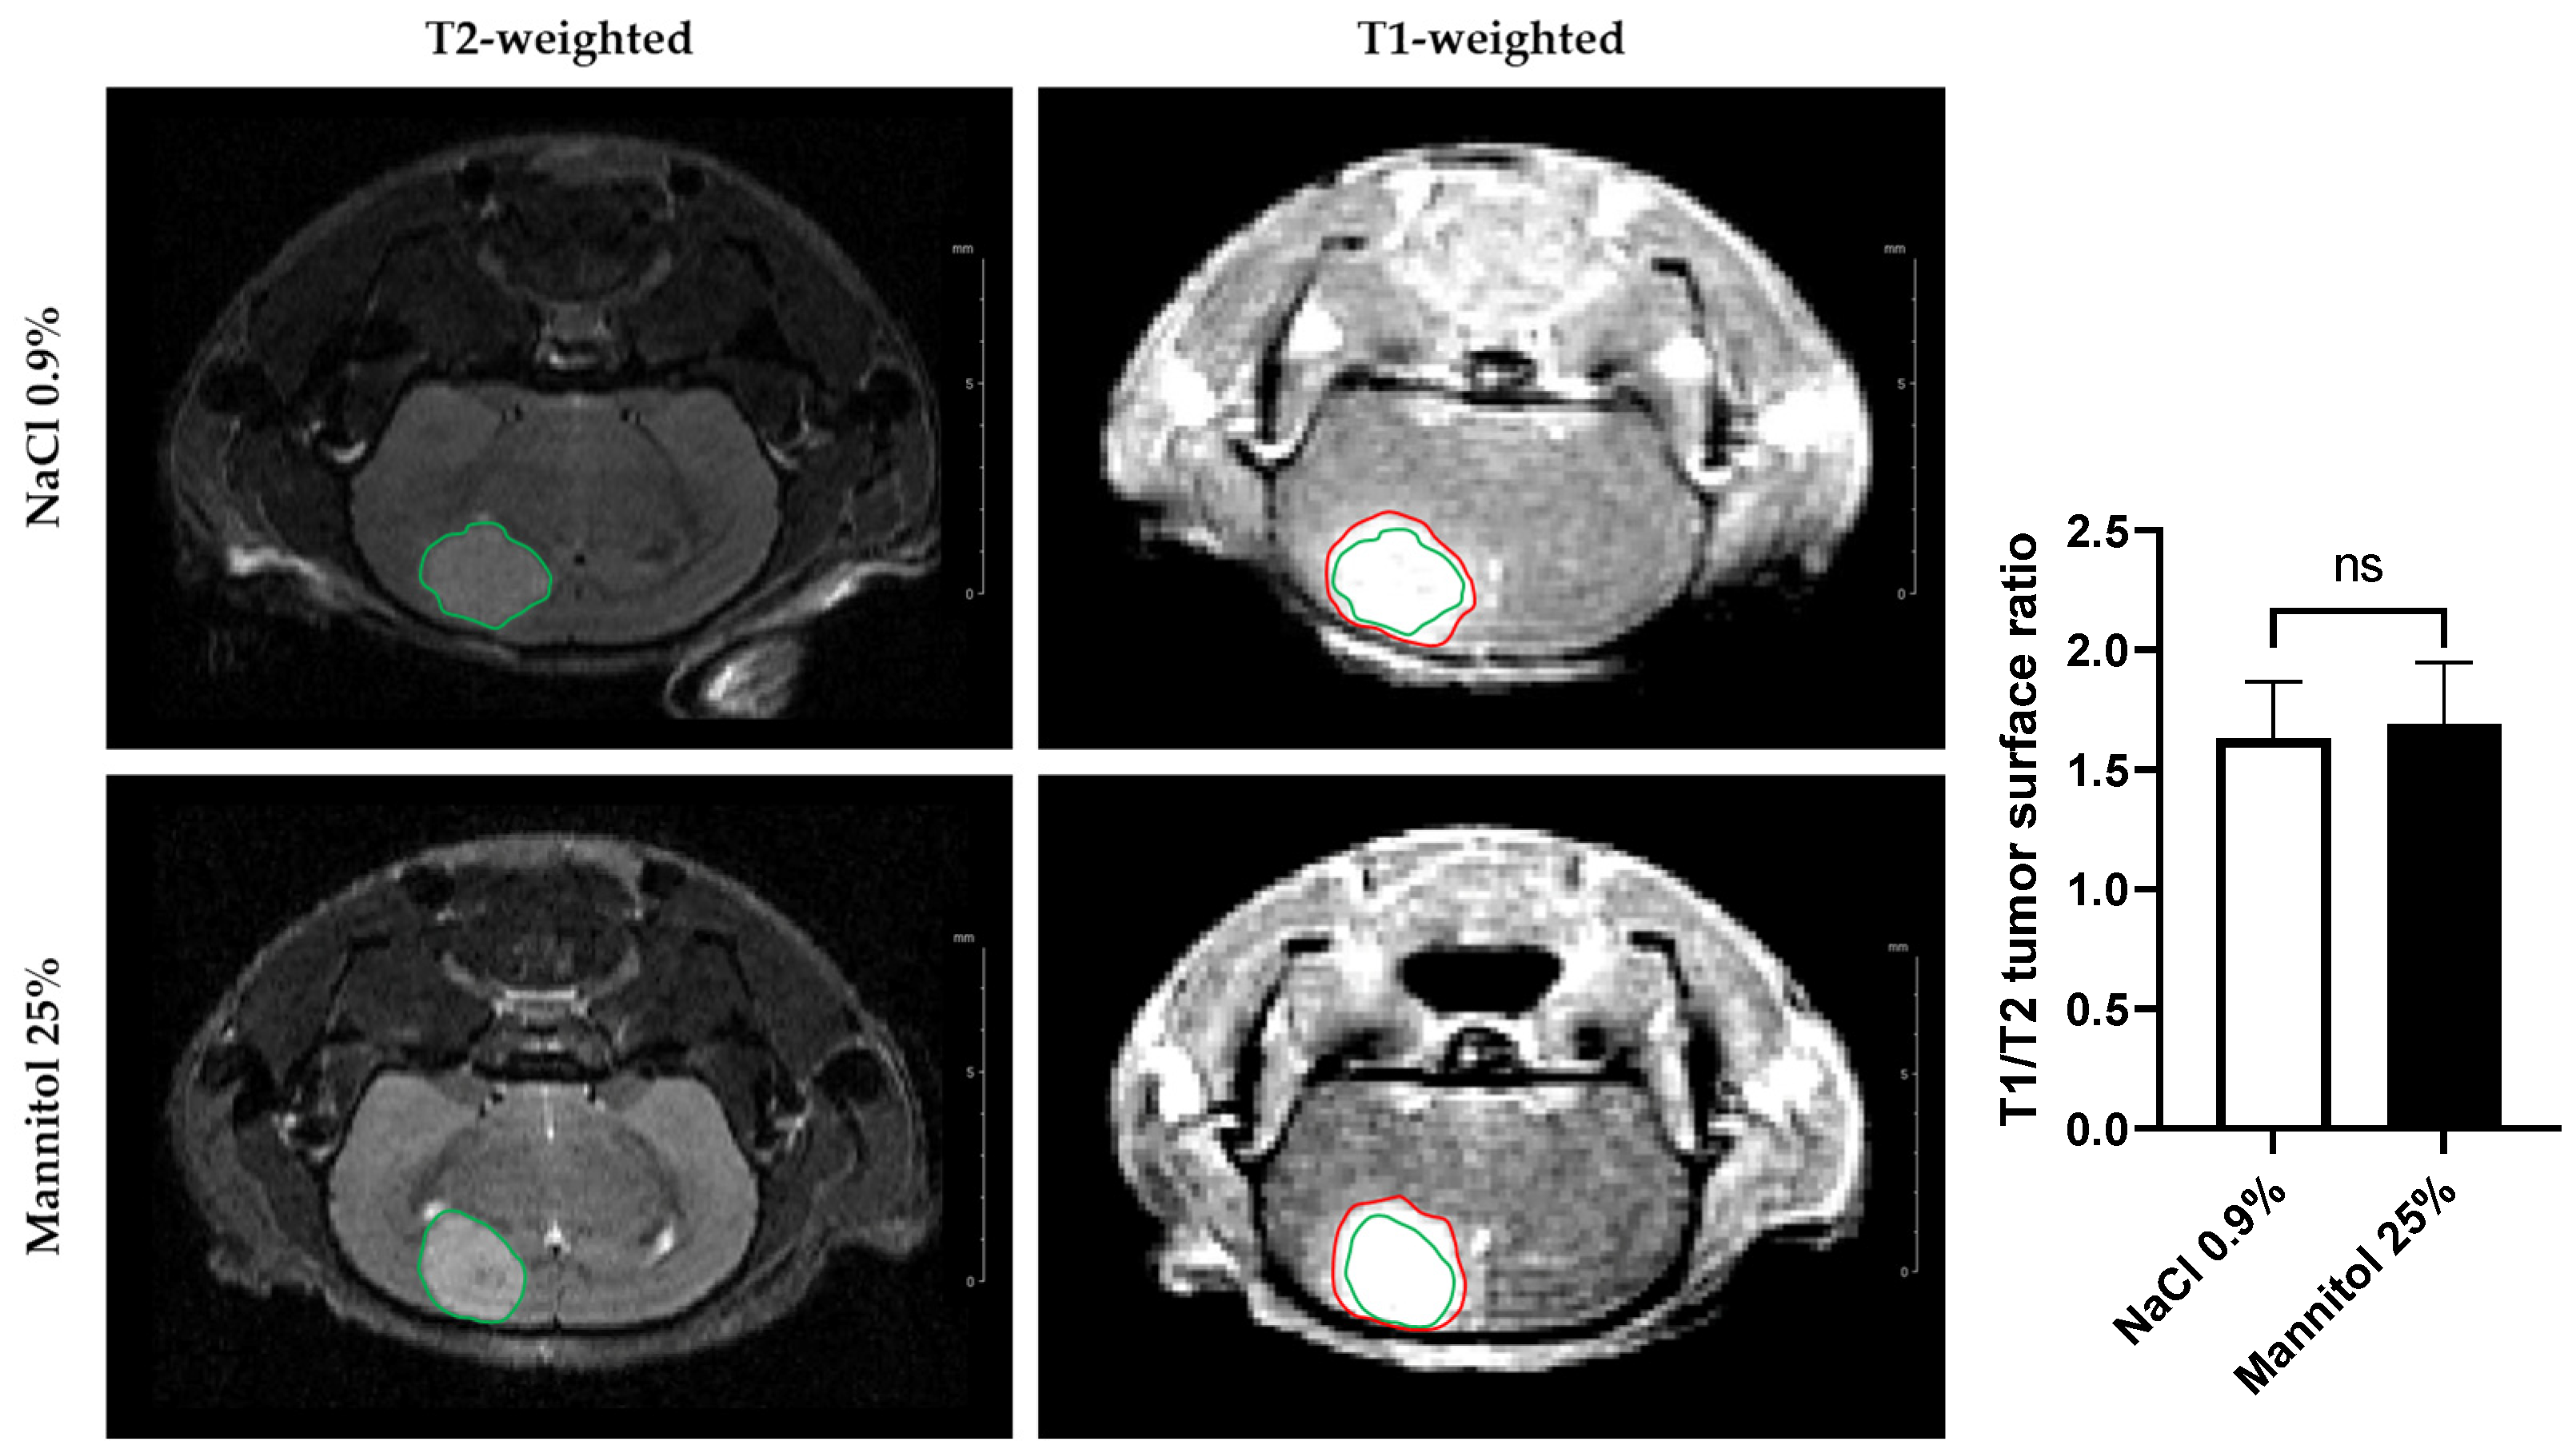

3.2.1. T1/T2 Tumor Surface Ratio

3.2.2. DCE-MRI